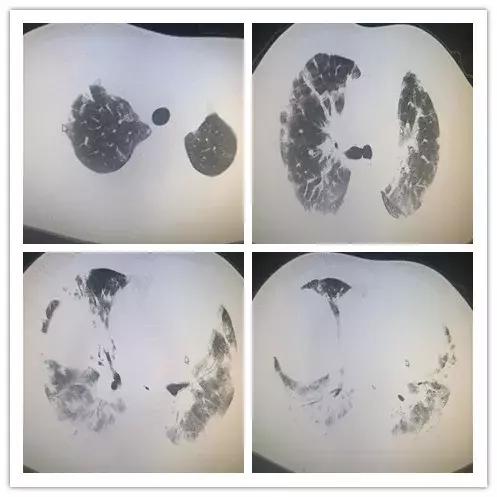

继续予以呼吸机辅助呼吸,同时调整抗感染治疗方案为美罗培南联合万古霉素及伏立康唑抗感染,同时继续予以甲强龙抗炎及乌司他汀治疗。复查胸部CT示:双肺多发磨玻璃影,斑片影,边界不清,密度不均,双侧胸腔少量积液。(图2)

【图2】2017年10月13日胸部CT